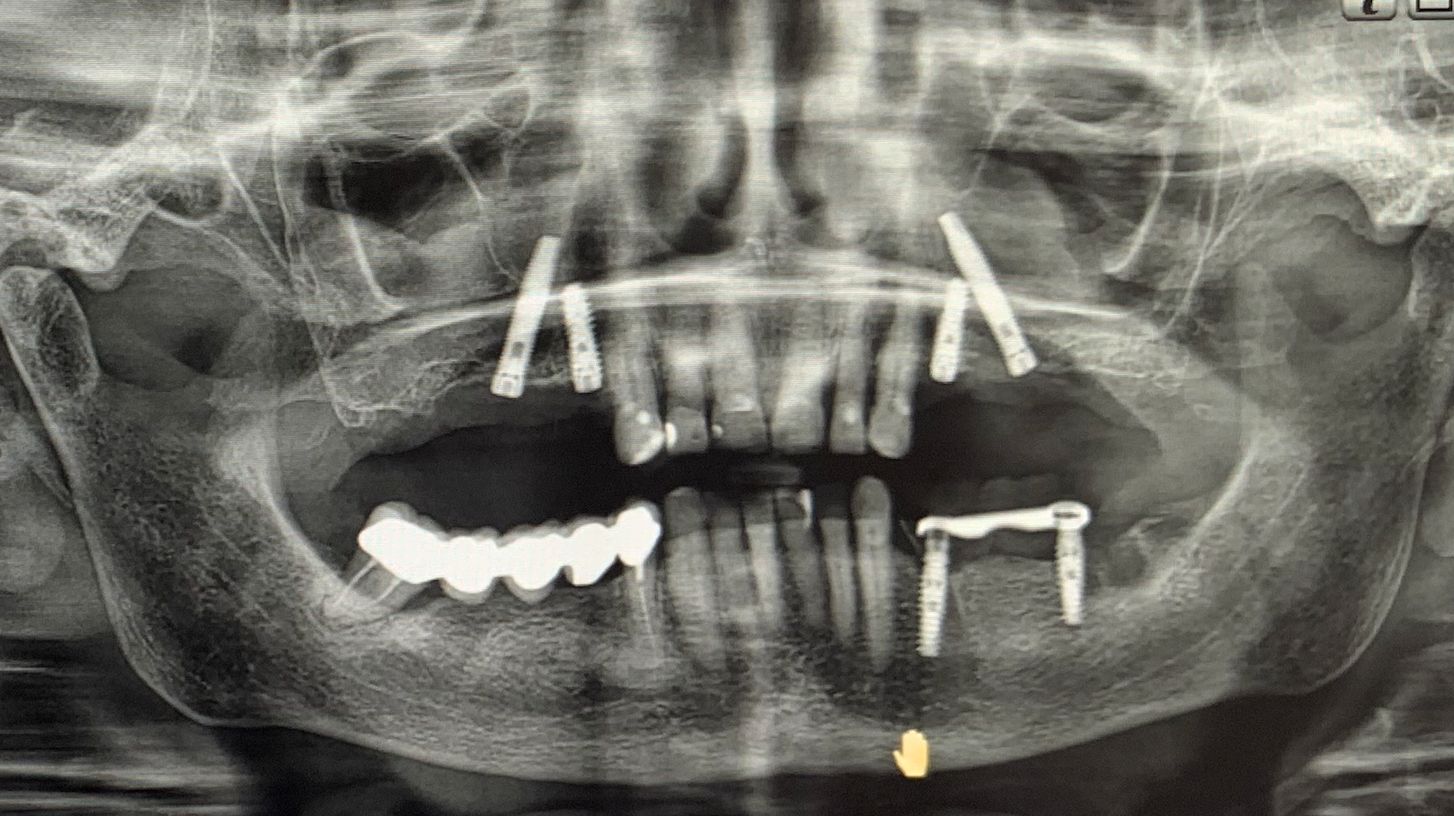

Nei settori posteriori, caratterizzati da significativa atrofia ossea e da pneumatizzazione del seno mascellare, è stato adottato un approccio transinusale. È stata pertanto realizzata una finestra laterale per consentire il sollevamento della membrana di Schneider (Fig. 3), procedura eseguita con particolare attenzione per preservarne l’integrità. Successivamente i siti implantari sono stati preparati con una traiettoria inclinata che attraversa la cavità sinusale, permettendo l'ancoraggio nell'osso basale anteriore. Sono stati quindi inseriti due impianti BT-Rhyno (Fig. 4), progettati specificatamente per l'inserimento transinusale e in grado di garantire adeguata stabilità anche in presenza di ridotto spessore osseo crestale.

Fig. 4 - Impianti BT-Rhyno

Al termine della fase implantare è stata eseguita una rigenerazione ossea localizzata intorno agli impianti posteriori utilizzando osso autologo prelevato mediante bone scraper (Fig. 5). Questo passaggio ha consentito di colmare eventuali spazi peri-implantari, favorendo i processi di osteointegrazione e contribuendo a migliorare la prognosi a lungo termine.

L'intervento è stato completato in un'unica seduta chirurgica, adottando un approccio minimamente invasivo e nel pieno rispetto dei tessuti. Le immagini intraoperatorie illustrano chiaramente le principali fasi del trattamento: il posizionamento degli impianti anteriori IS+, l'inserimento transinusale degli impianti BT-Rhyno e l'applicazione di osso autologo per la rigenerazione finale (Fig. 6).